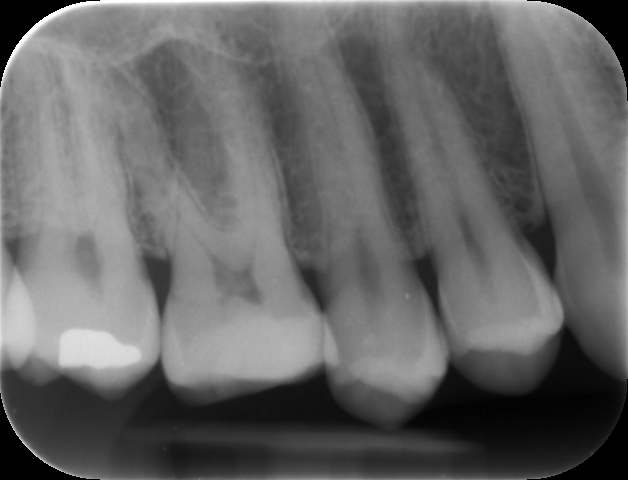

Il caso è di un maschio 46enne con l’elemento 16 (primo molare superiore di destra) presentante otturazione di amalgama infiltrata. Dopo aver effettuato i 4-5 tests clinici valutativi, si è eseguita l’anestesia locale e iniziata la rimozione della stessa e della dentina cariata.

Dopo aver scoperto parte della camera pulpare (la zona in cui è presente il “nervo”) si è proceduto ad eseguire l’incappucciamento diretto con BIODENTINE (septodont), un materiale appartenente alla classe dei cementi portland con una elevata biocompatibilità e caratteristiche meccaniche molto simili a quelle della dentina naturale.

Dopo quasi due mesi si è proceduto alla preparazione della cavità e alla realizzazione dell’impronta per la realizzazione di un intarsio in composito rinforzato.

Si può notare la risposta positiva della polpa e la soddisfazione del paziente nell’avere, a distanza di più di un anno, il suo dente ancora vitale.